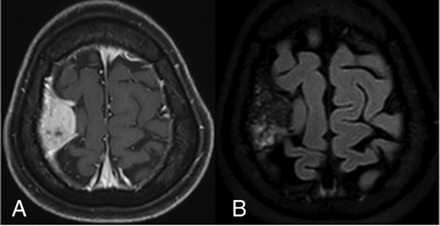

Hypointensity on T2WI is a feature that is not commonly seen in meningiomas and generally indicates hypercellularity, large areas of calcification, or significant fibrous tissue in the tumor, which are variably present in meningioma mimics. In this study, 25.8% (8/31) of malignant dural-based tumors showed hypointensity on T2WI. They were metastases, plasmacytoma/multiple myeloma, and osteosarcoma (Fig 4). The frequency of hypointensity on T2WI was lower compared with the findings of Starr and Cha,2 in which 43% of malignant dural-based tumors had hypointensity on T2WI. Homogeneous or heterogeneous enhancement on T1WI was variable in each tumor type and histologic subtype of meningioma.22

A, CE-T1WI fat suppression sequence demonstrates an extra-axial mass at the right frontoparietal convexity with a dural tail sign that resembles a meningioma. B, CE-FLAIR sequence. No rim enhancement on the tumor-brain interface is observed. Meningioma was the favored diagnosis in the initial report. The pathologic result was osteosarcoma.